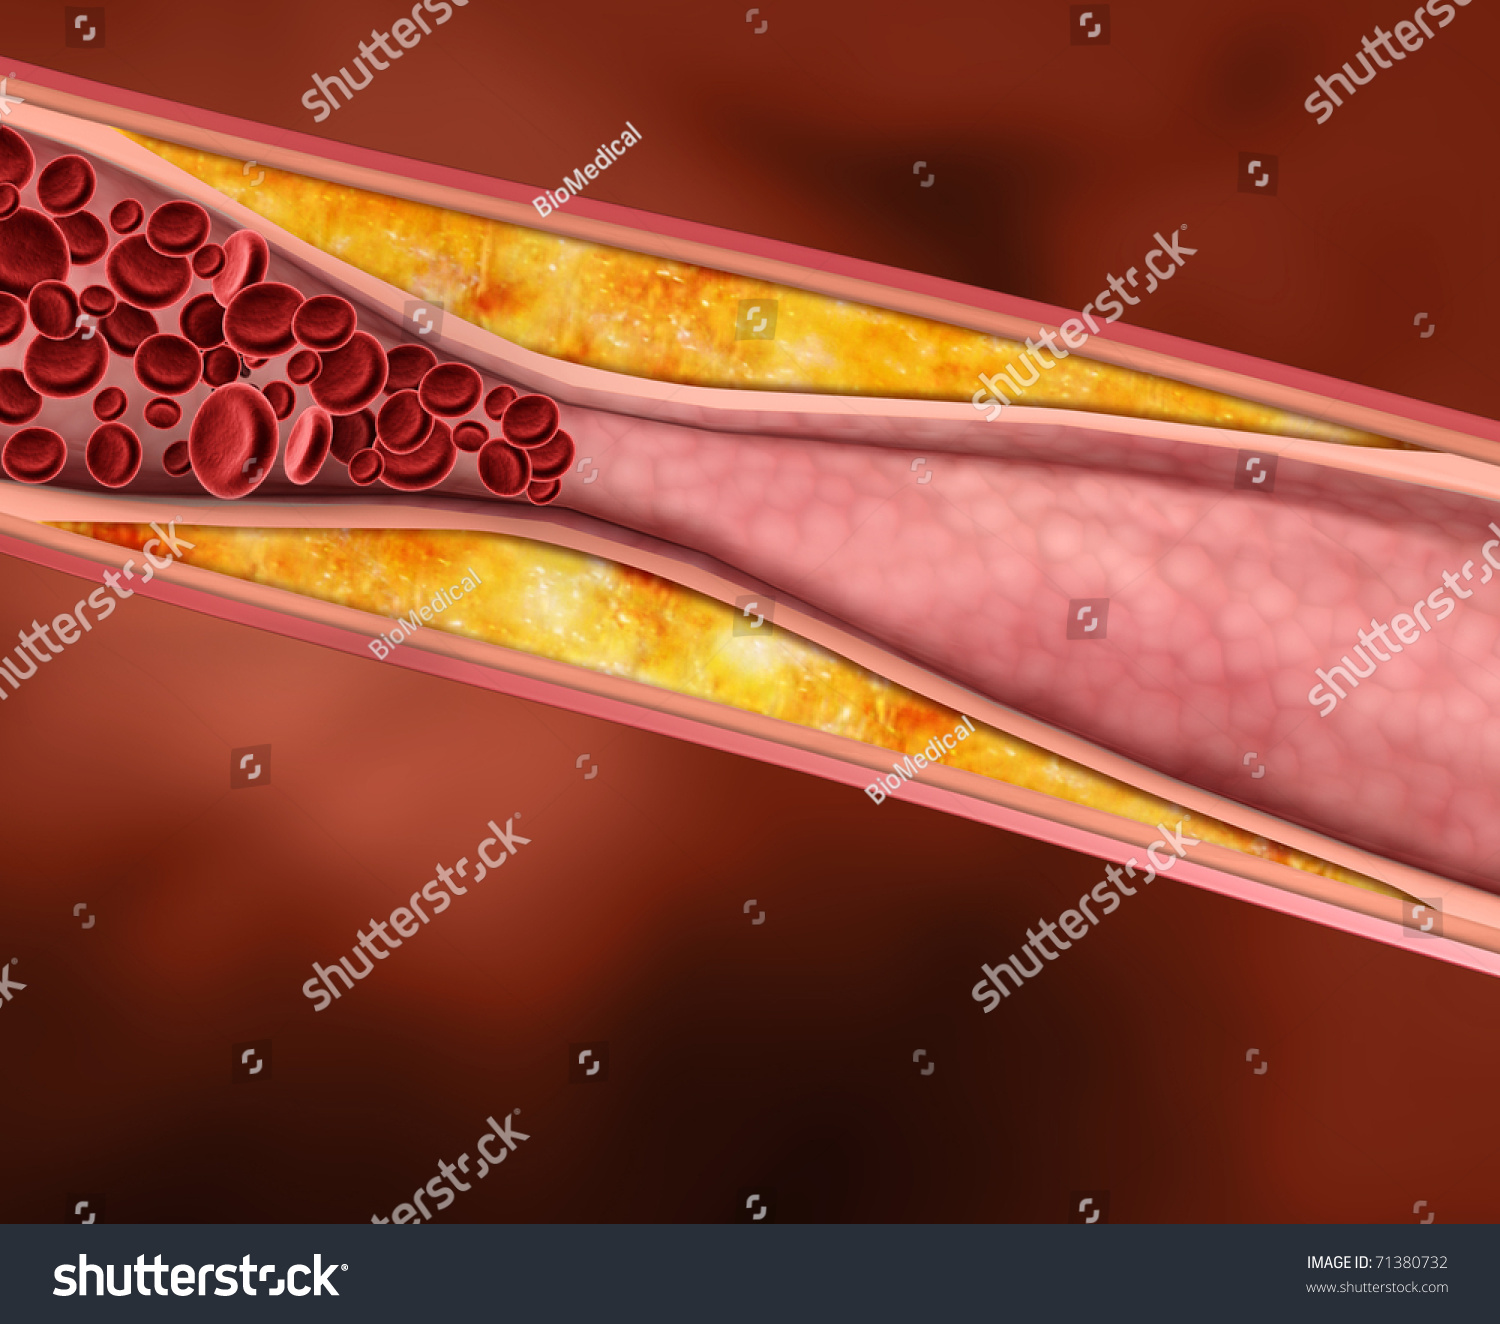

a deposit of plaque within the arterial wall

Cholesterol plaque in artery – Vida Abuelo

Artery Blockage caused by Plaque – TrialExhibits Inc.

Blood Clot, Plaque In Artery Restricting Blood Flow Stock Photo …